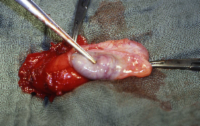

Die abgekapselten Tumoren (benigne bzw. maligne) sind auf der Schnittfläche von gelb-brauner Farbe (Abbildung 4). Histologisch finden sich verschieden große polygonale Zellen, leicht vakuolisiert, zumeist in großen Haufen. Selten mit kristalloiden Einschlüssen (Reincke-Kristalle) in 40%, z.T. mit Aufhellungen des Zytoplasmas (Abbildung 5).

Bei der Hodenfreilegung fand sich makroskopisch ein Tumor von inhomogener Konsistenz, scharf abgegrenzt und von einer Kapsel umgeben, die Farbe des Tumors war bräunlich-gelblich. Hoden und Nebenhoden wurden entfernt (s. Abbildung 4). Histologisch wurde an dem entnommenen Gewebe ein Leydig-Zell-Tumor diagnostiziert (s. Abbildung 5). Morphologische maligne Kriterien lagen nicht vor. Weitere theraupeutische Maßnahmen außer Orchidektomie waren daher nicht erforderlich. Bei den postoperativen Nachkontrollen zeigten die erhöhten Östradiolwerte eine Normalisierung.